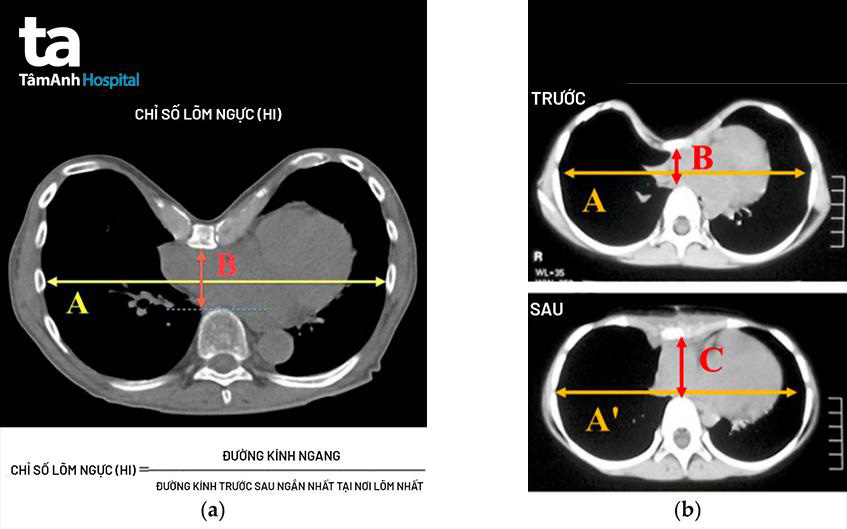

BS.CKII Nguyễn Đỗ Trọng, khoa Phẫu thuật Tim mạch – Lồng ngực, Trung tâm Tim mạch BVĐK Tâm Anh TP.HCM thông tin, lõm ngực bẩm sinh (hay còn gọi là ngực phễu) là dị dạng thành ngực bẩm sinh thường gặp nhất ở trẻ em và thiếu niên, xảy ra với tỷ lệ 1/300 – 1/400 trẻ sơ sinh và chiếm 90% trong tất cả biến dạng lồng ngực. Bệnh thường gặp ở trẻ trai hơn so với trẻ gái. Dị tật này có liên quan đến yếu tố gia đình (35%), vẹo cột sống (21%), có thể kèm theo các hội chứng bẩm sinh khác (Marfan, Ehlers-Danlos, Poland…).

Lõm ngực là tình trạng phát triển bất thường của khung xương sườn. Trong đó, xương ức phát triển vào trong, gây ra vết lõm ở thành ngực. Mặc dù xương ức lõm xuống thường dễ nhận thấy ngay sau khi sinh, nhưng bệnh lý này thường trở nên trầm trọng hơn trong giai đoạn phát triển vượt bậc của tuổi vị thành niên.